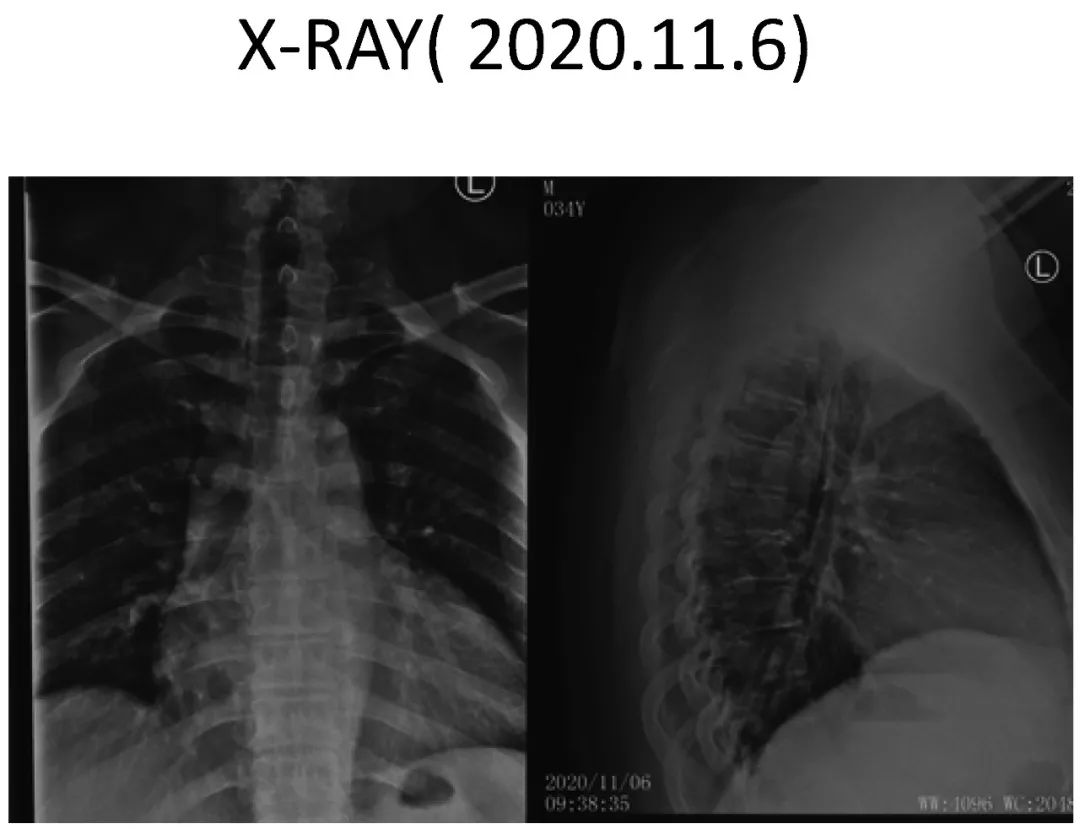

影像资料:

Thoracic spinal stenosis(T2-T3)

Thoracic spinal stenosis decompression(T2-T3)